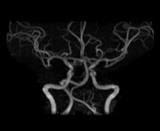

マア 脳MRI, 脳血管、脳MRA 全て問題なしでした♪